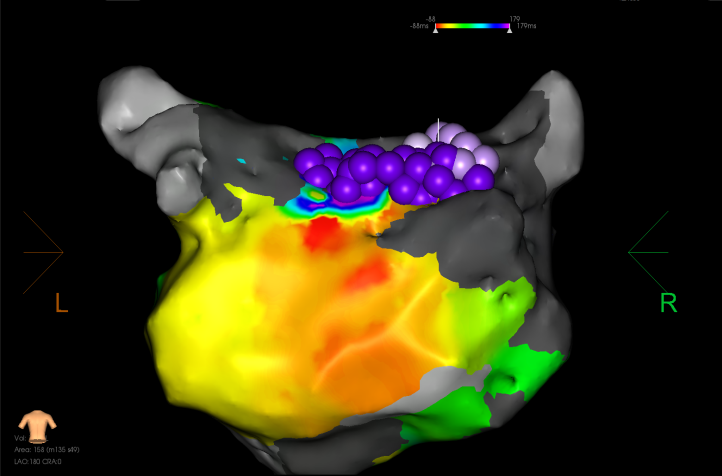

激动图显示为绕着前壁瘢痕区的折返,后壁为被动传导。

前壁瘢痕折返激动图

激动从后壁沿着底部和左侧向前壁激动,形成顶部依赖的大折返。

顶部依赖折返激动图